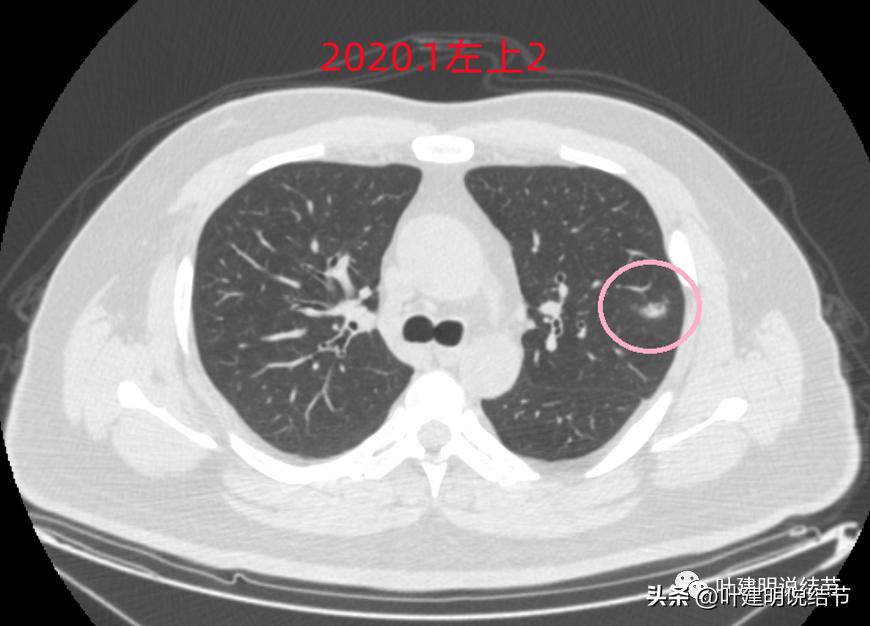

左上病灶1:磨玻璃结节,轮廓清楚伴微血管进入,中间似乎有空泡征,感觉像原位癌或不典型增生;

左上病灶2:混合磨玻璃结节,密度偏高,边缘稍糊,但轮廓相对清,有微血管分支进入,考虑微浸润性腺癌或浸润性腺癌可能大;